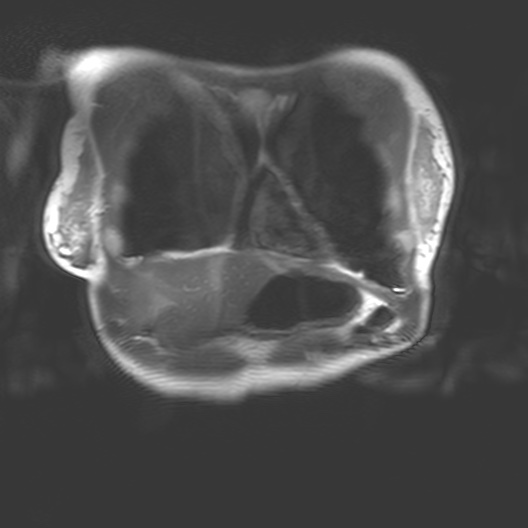

Corporeal matter as perceived by MRI straddles definitions of substance, organism, subject and object. MRI interacts with the body through nuclear magnetic resonance and electrodynamics, bringing us into contact with the body as a person, as an assemblage of biochemical reactions, as a patient and a cellular, molecular, atomic and subatomically composed entity.

MRI is a non-invasive biomedical imaging technology that visualises tissues within the body. MRI is an interesting piece of physics that interacts with the body. As a technology it draws on the quantume mechanical properties embedded in corporeal matter - particularly hydrogen ions, also known as protons (H+). MRI brings together multiple aspects of our ontology. MRI interacts with the body through nuclear magnetic resonance and classical electrodynamics and thus physics allows us to connect to the abject. This brings us into contact with the body as a person, a patient, a member of a community, and as a cellular, molecular, atomic and subatomically composed entity.

I began my investigation by taking part in MRI trials at the Cancer Centre in 2018 with Dr Heather Fitzke. MRI images confront us with the fact that our bodily materiality acts beyond us and that medical technology shapes our sense of self.

Seeing my organs autonomously pulsing on the monitor in the control room had a pronounced impact on me. It was like looking into a rockpool within my own body. The affecting power of MRI (its power to change our emotions) is in its potential to reveal autonomic bodily functions and diseases which are beyond our control. The data on the screen revealed my autonomous self: peristalsis, bowel movements, digestion, heartbeats and respiration. Through MRI, anatomy is seen as embedded and relational.

I felt a deep sense of fascination with how my organs moved and worked. Haraway’s situated biopolitics argues for an account of the body as an environment, in a state of simultaneous dissolution and formation which I notice in my data. My organs seemed like invertebrates in a rockpool: a squishy pulsing ecosystem. Organs do not operate in isolation but are interconnected. Their autonomous pulsing and motion seemed creaturely and strange in contrast to my numerous encounters with preserved cadavers in the dissecting room. My organs keep me alive yet I have no conscious sense of their functioning. They function beyond me.